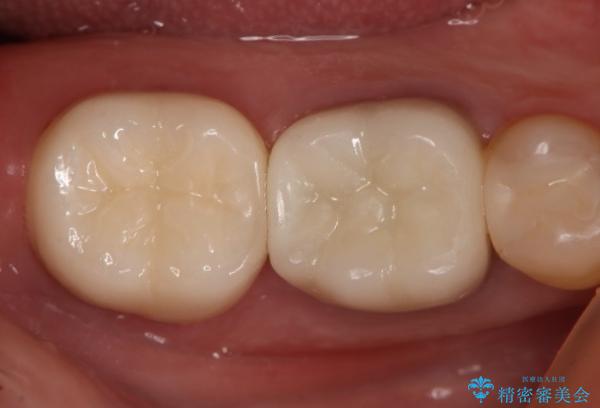

痛みは完全に取り除かれ、咬合時の違和感もなく経過は良好です。